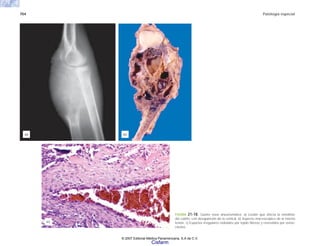

vasomotor

vasos